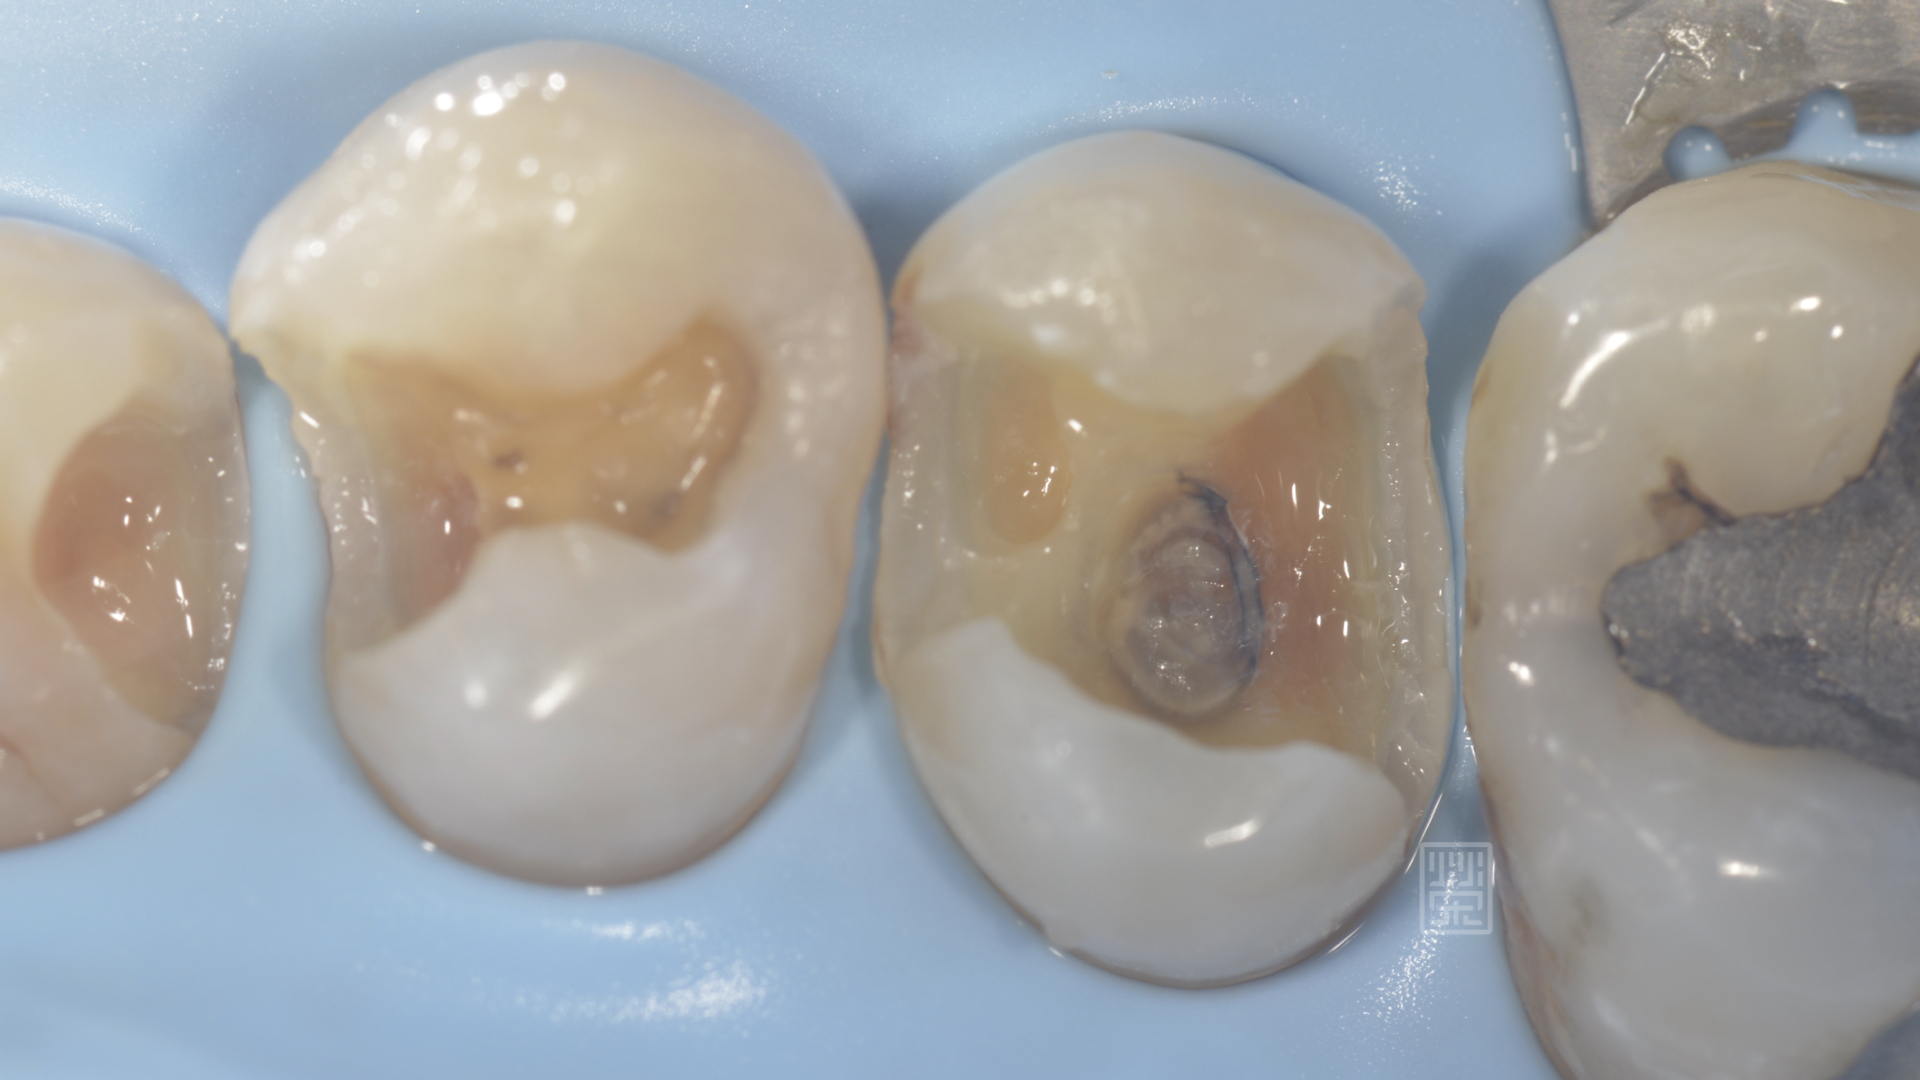

當把填補物與蛀牙清除後,發現蛀牙比預想的還大

除了內部蛀牙外,外側也因清潔不當所造成的蛀牙